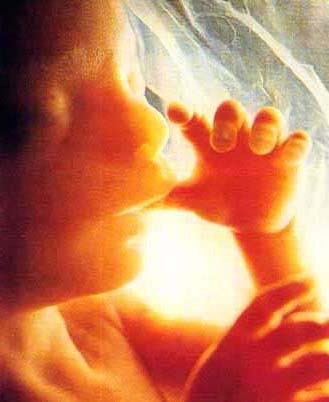

Parto cesareo: 10 falsi miti da sfatare

È meno doloroso e più sicuro rispetto al parto naturale? Lascia una grande citatrice visibile? Impedisce di allattare al seno? Sono tanti i falsi miti da sfatare intorno al parto cesareo. Scopriamone 10

È meno doloroso e più sicuro rispetto al parto naturale? Lascia una grande citatrice visibile? Impedisce di allattare al seno? Sono tanti i falsi miti da sfatare intorno al parto cesareo. Scopriamone 10